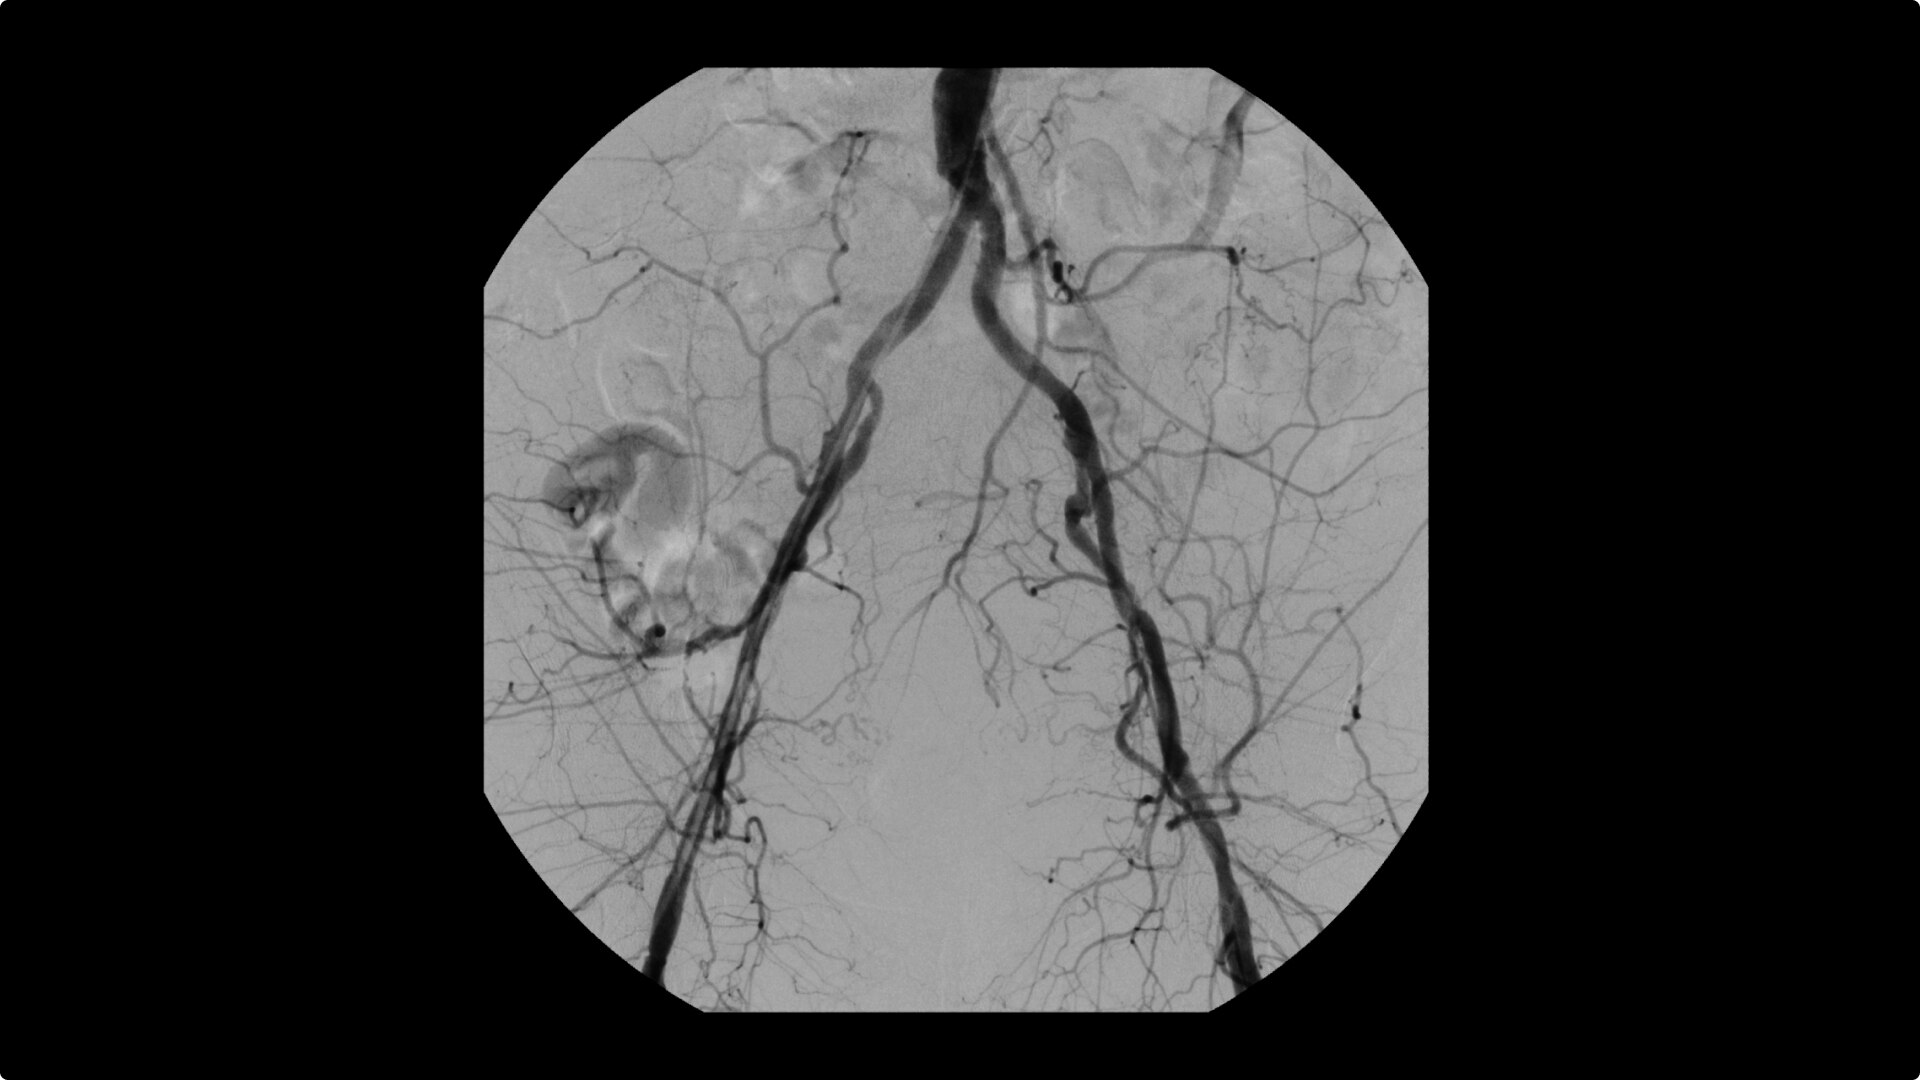

Complex vascular procedures require powerful imaging systems. OEC premium C-arms perform in a variety of procedures such as:

•Abdominal aortic aneurysm (AAA) stent and balloon deployment

• Atherectomy

• Dialysis declot

• Infrarenal aortic aneurysm repair

• Recanalization and stent placement in iliac arteries

• Recanalization of the superior mesenteric artery

• Stent implant in peripheral artery

• Vascular long lesion treatment